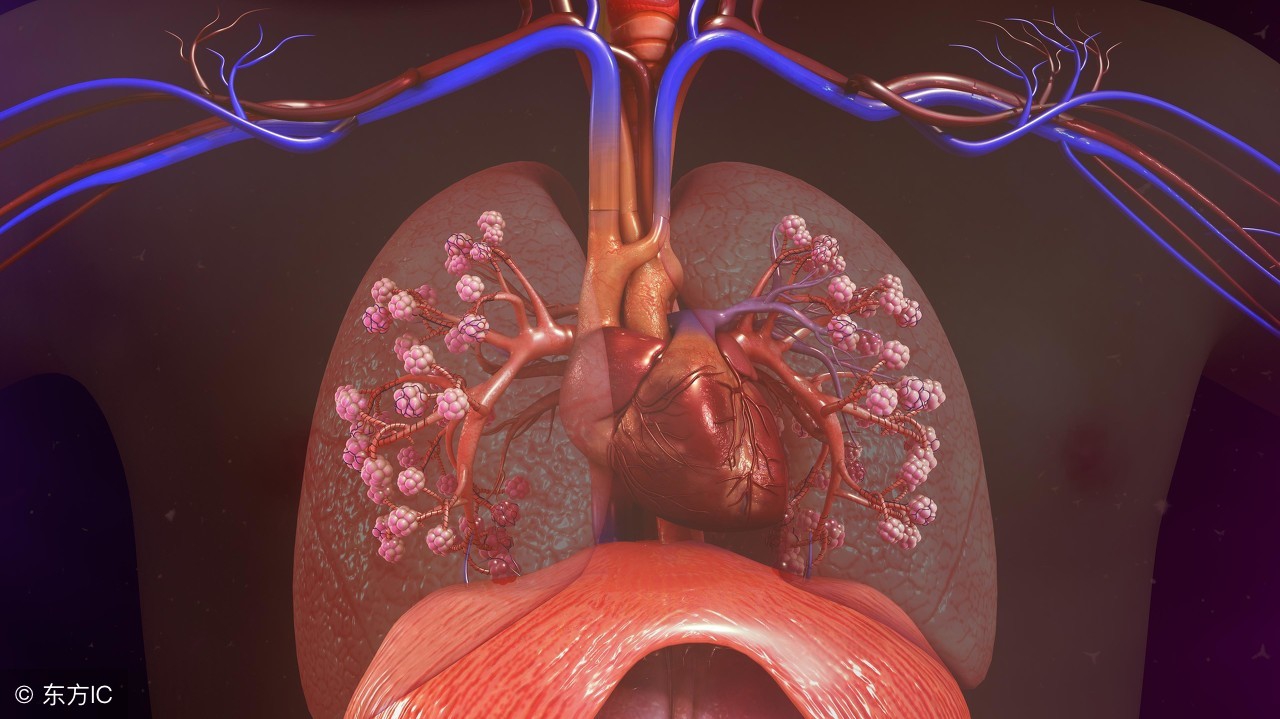

什么是肺大疱?肺大疱又称肺大泡,指的是由于某些特殊的因素,例如患者体内肺泡的腔内的内外压力不一致,也就是内部压力过高导致用来保护肺泡内部结构的肺泡壁被直接损坏,即涨破,从而在患者的肺部形成了新的物质、组织或者结构等的一种疾病。这种疾病分先天性的和后天性的,前者一般是出现的人群以小孩子为主,而后者则是那些已经成年的人并且多见于老年人。

肺大泡本身是一种无声无息的疾病,甚至患者根本没发现自己身上出现了肺大泡,如果是小小的肺大泡当然不会引起患者出现症状,但是它可能会逐渐的长大甚至可能在其他人体的位置也出现了新的肺大泡,一般情况下肺大泡是不会表现出明显的症状的,甚至是一直潜伏在人体体内。等到疾病爆发的时候问题就可能是很严重了,随着肺大泡的增长,患者可能会因为其增大出现胸闷、气短的现象,并且伴随并发症,即气胸,并且单单在气胸这种的并发症上就有好几种类型:像自发性的气胸、感染性的气胸等等。